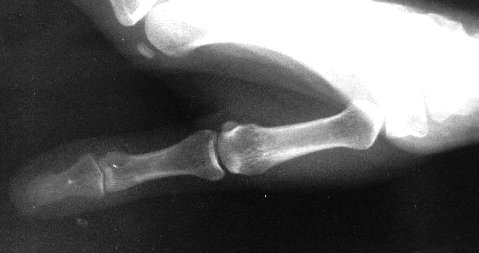

Roberts thumb Xray view

Xray beam angle 90 degrees.

This is really an AP of the thumb.